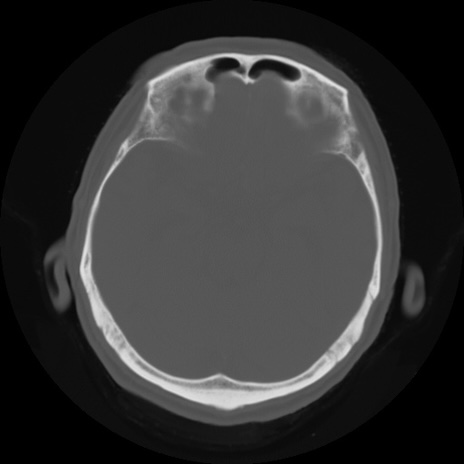

【頭部】症例5 CT(横断像)

【症例】80歳代 男性

【主訴】頭部打撲

【現病歴】外出先で椅子から立ち上がる際に、つまづいて後方へ転倒し受傷。転倒時に意識はあった。

【既往歴】高血圧、不整脈、アルツハイマー病

【身体所見】BP 217/71、HR 96、JCS1-1、 難聴あり、顔色良好、右後頭部に擦過創あり。神経学的異常なし。

症例5の画像所見と診断は?